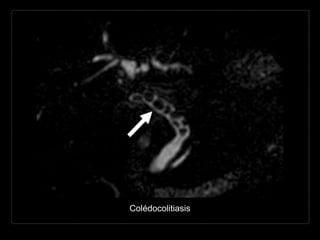

Hallazgos por RM

• CPRM (RARE - HASTE)

• bilis: muy hiperintensa

• cálculos: foco hipointenso

• defectos de llenado

hipointensos entre la bilis

hiperintensa.

• T1

• apariencia variable.

Colédocolitiasis